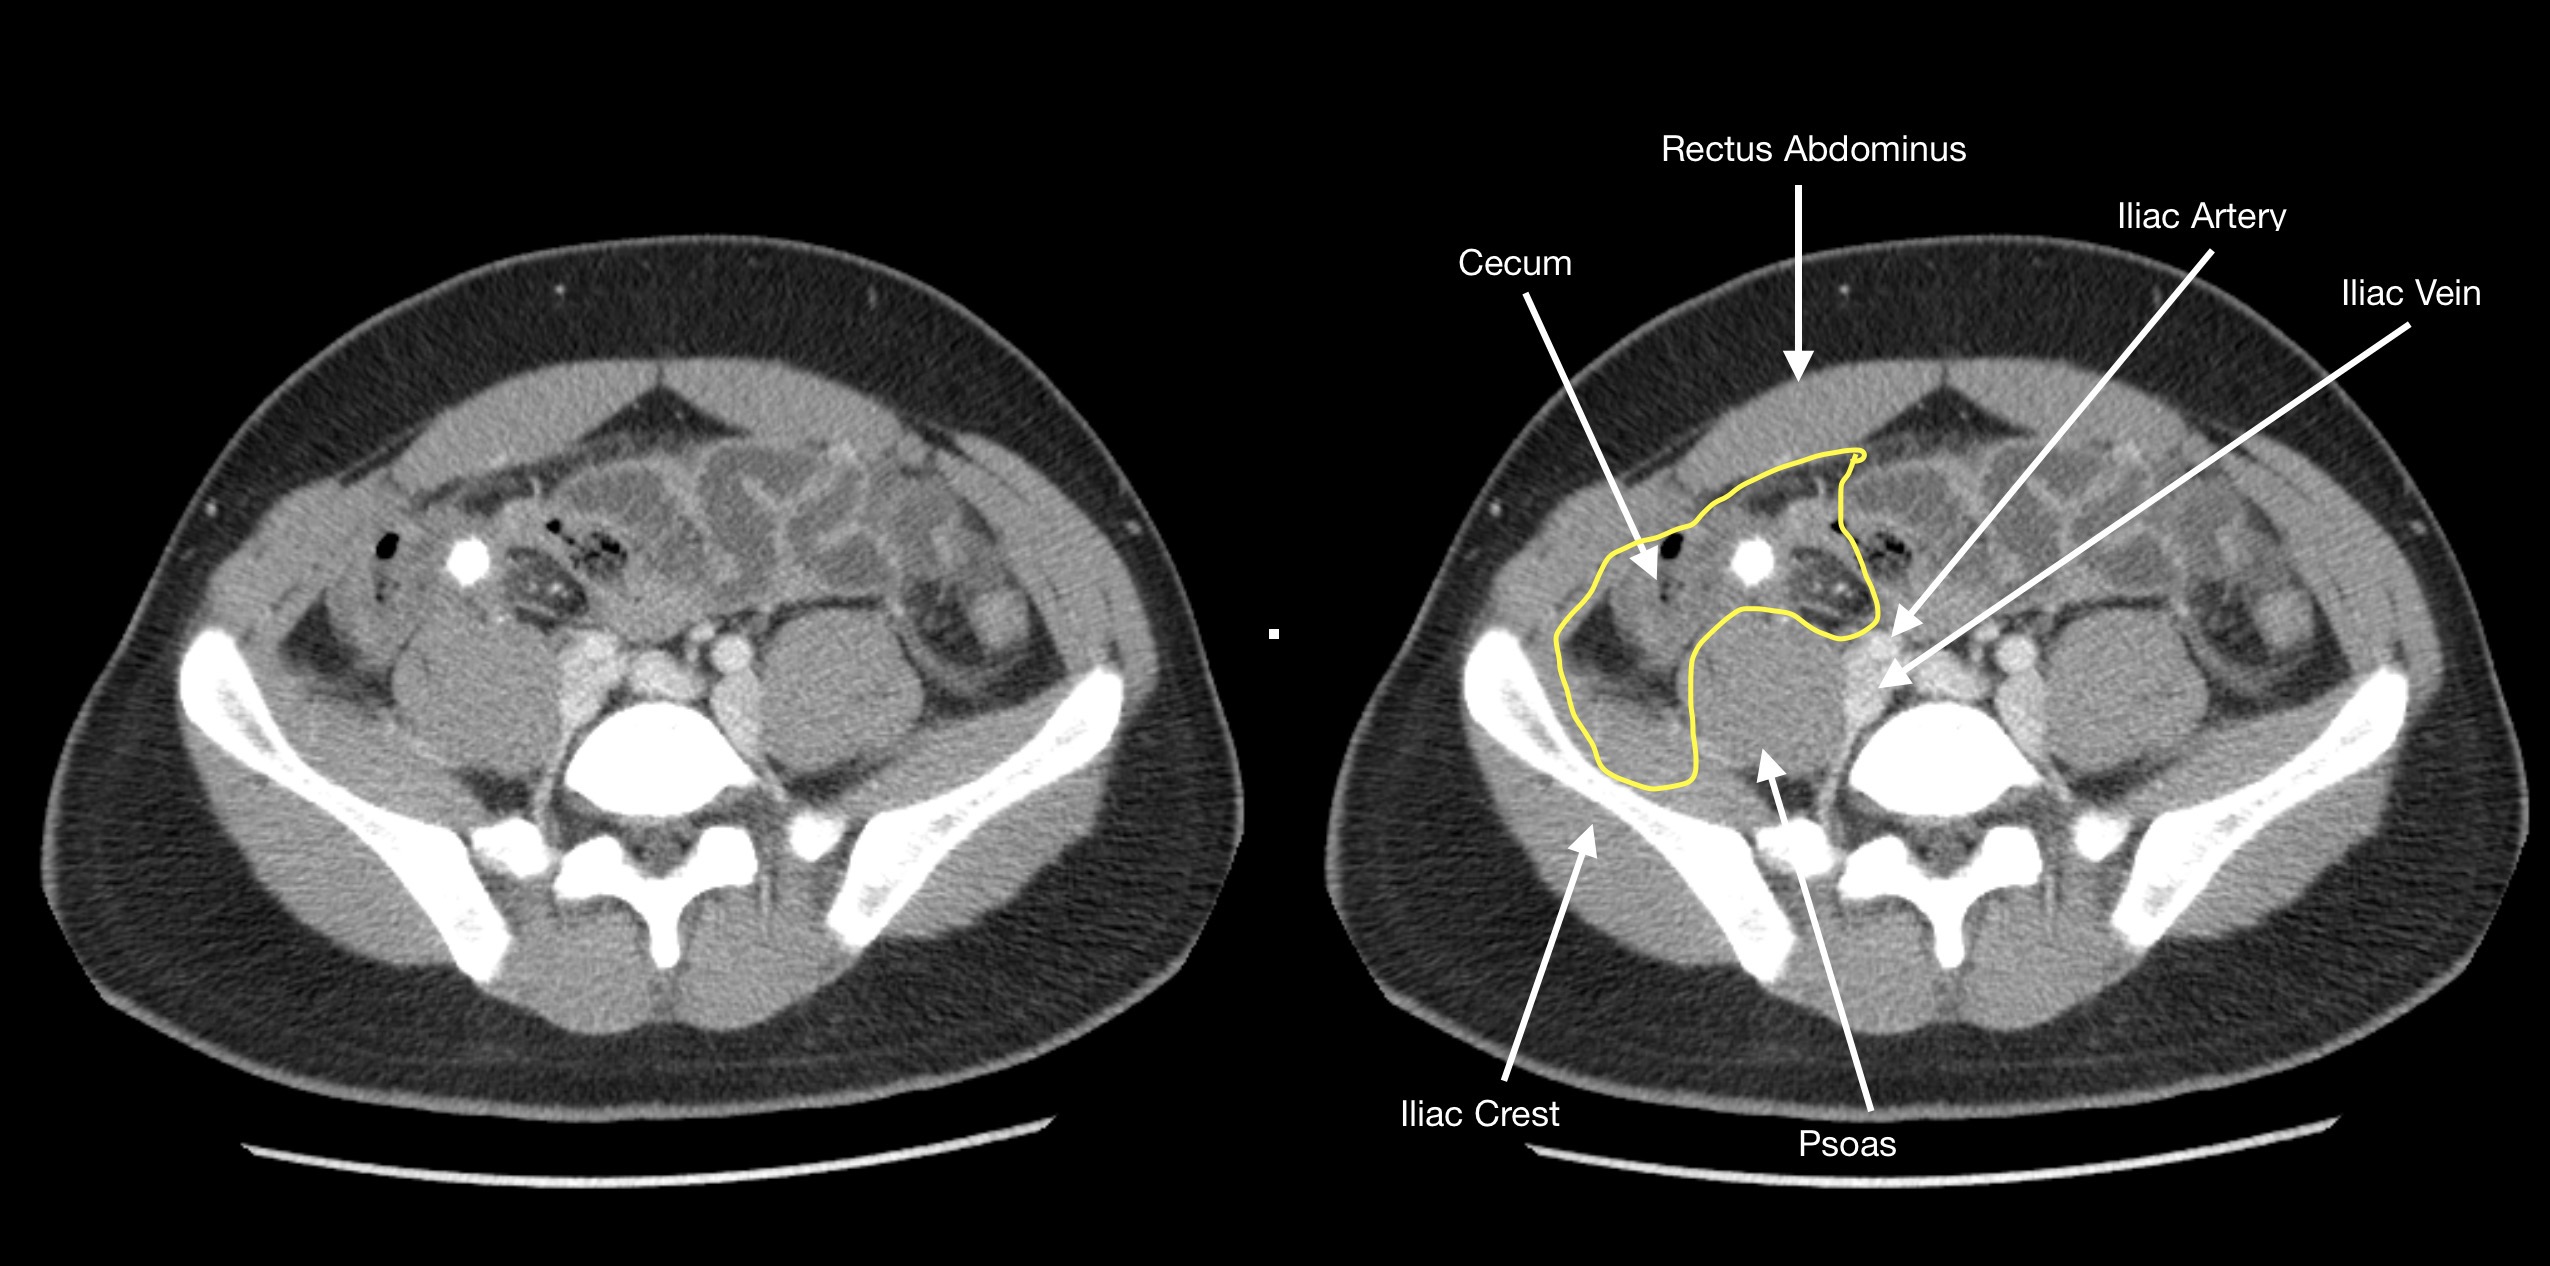

How To Find The Appendix On Imaging Stepwards

The normal caliber of a collapsed appendix on computed tomography (CT) is generally accepted as ≤ 6 mm and can be identified in 43-100% of patients depending on factors such as contrast enhancement and slice thickness (Figs. 3a, b) [].However, if distended by air or contrast material, a normal appendix can measure up to 10 mm.

Among these patients, the mean diameter of the normal appendix was 5.6-5.7 mm, with a normal range (95% CI) encompassing 2.7-8.7 mm and 34-39% of normal appendixes measuring greater than 6 mm in diameter. Although this represents a much larger sample than prior studies, the mean normal appendiceal diameter is concordant with diameters.

CT appearance of the normal appendix in adults Semantic Scholar